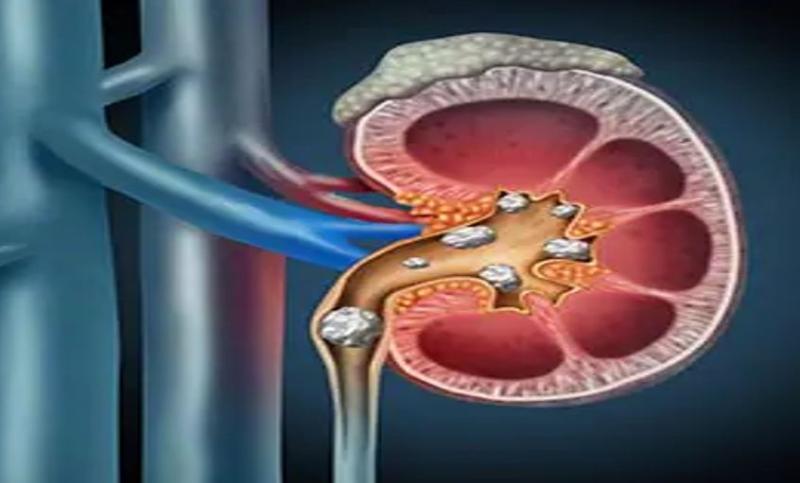

क्या होती है पथरी?

पथरी क्या होती है? दरअसल, जब हमारे पेट में आॉक्जालेट, कैल्शियम जैसे क्रिस्टल्स इकट्ठा होकर जमा हो जाते हैं, तो एक गठान जैसी संरचना बनने लगती है, ये ठीक पत्थर की तरह समान दिखती है। जिसे पथरी कहते हैं। पथरी की समस्या अधिकतर किडनी में होती है, इसलिए इसे किडनी स्टोन कहा जाता है।